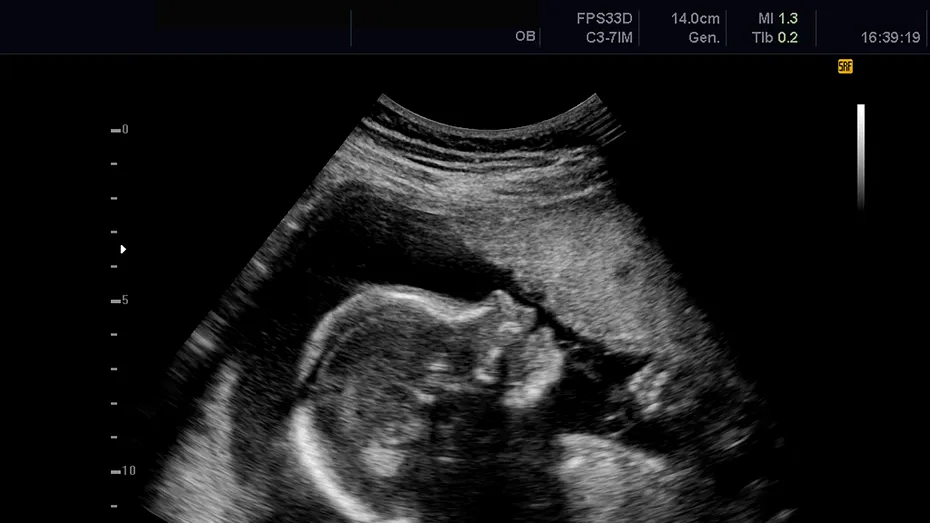

Ulterior, în urma unei scanări 3D, doctorii au descoperit că avea un făt calcifiat în burtă, numit lithopedion. Ea rămăsese ultima dată gravidă în 1968. Așadar, timp de 56 de ani, ea a purtat fetusul mort în pântece.